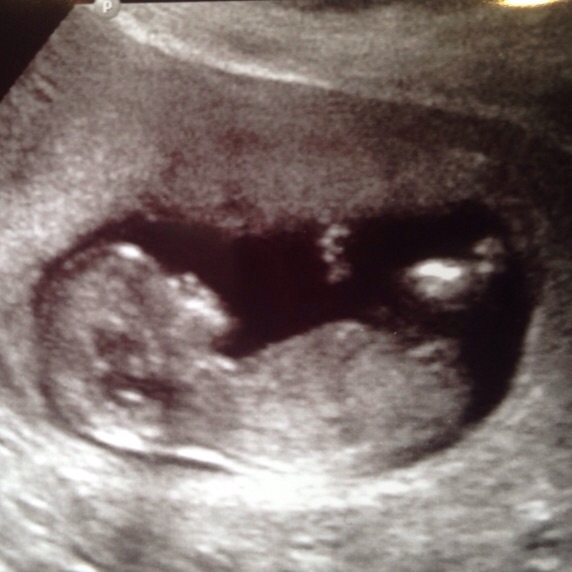

Any ideas whether this 12 week sono shows a baby boy or girl?? Lol

That is WAY to early to tell.

Based on the nub theroy I would say girl!

Based on the jaw line i would say it looks like a baby ..... And could possibly be a boy or a girl

This is a profile view...so no one can tell you. What did the u/s tech say?

We had the nuchal translucency test at week 12 and the doctor could tell the sex so it's possible

I just found out at 12 weeks 5 days girl I go back at 14 weeks to confirm. U can def tell if your ultrasound tech knows what they are doing.